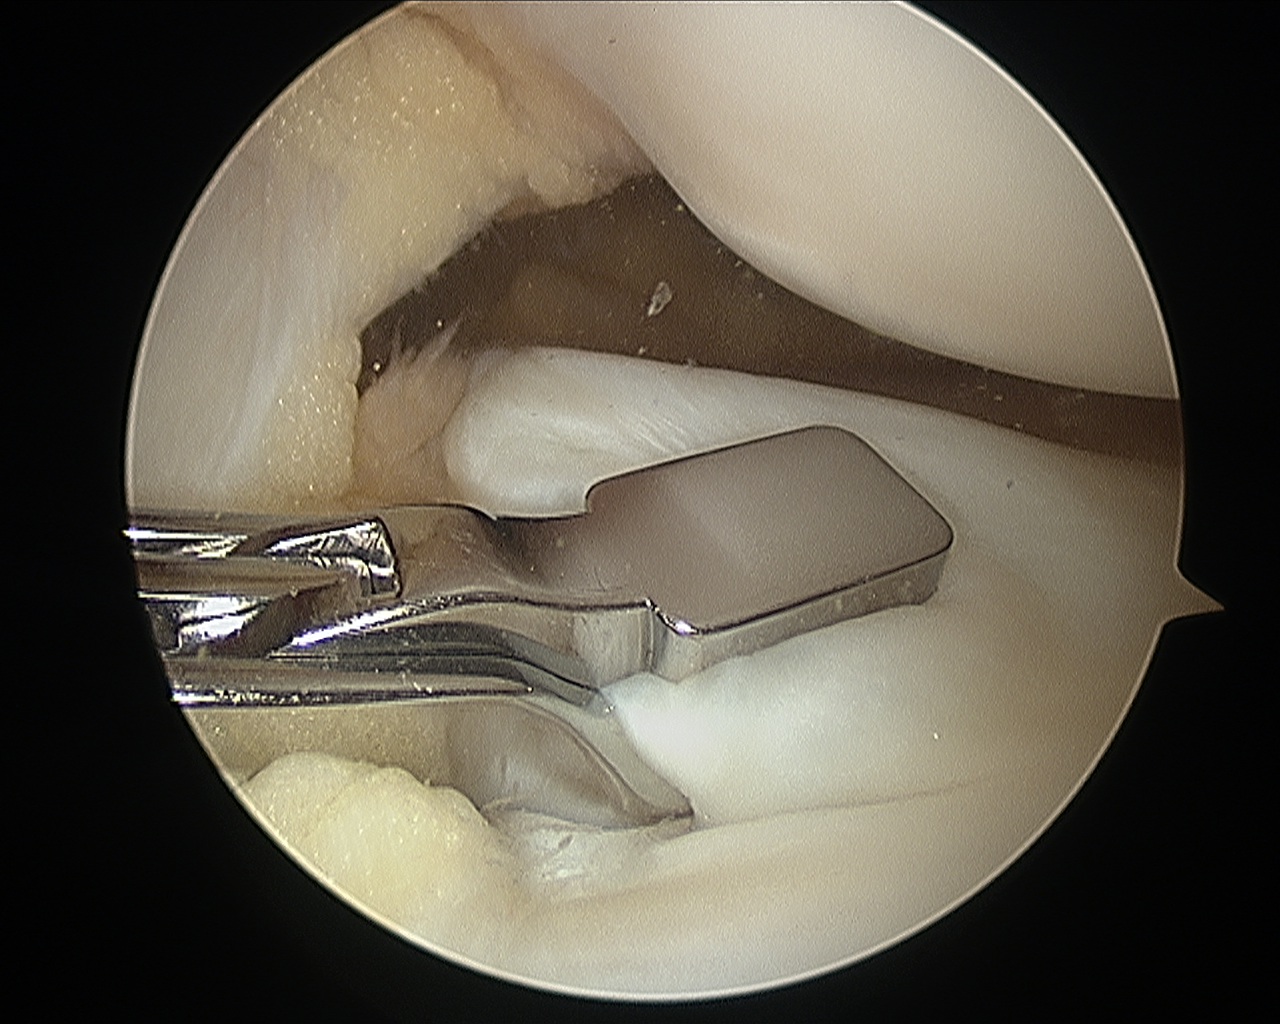

Αρθροσκοπική Αντιμετώπιση Παθήσεων Μηνίσκου